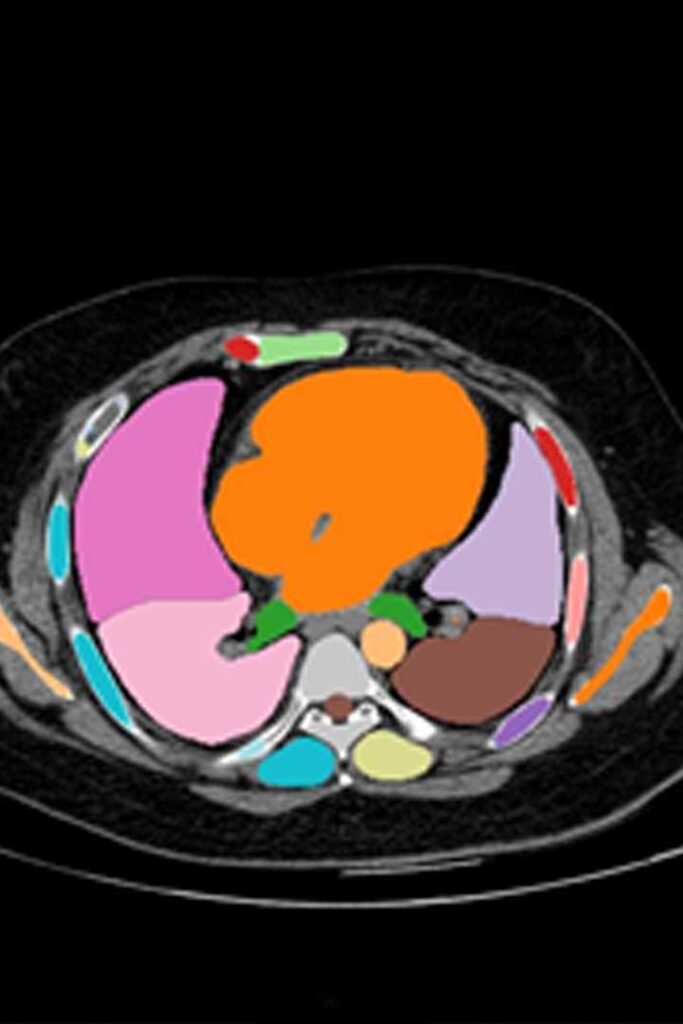

Full Body CT

TotalSeg

Performs full-body organ and tissue segmentation covering over 100 anatomical structures.

• Volumetric analysis & dose planning

• Quantitative research biomarkers

• Based on TotalSegmentator project

Zurich Research